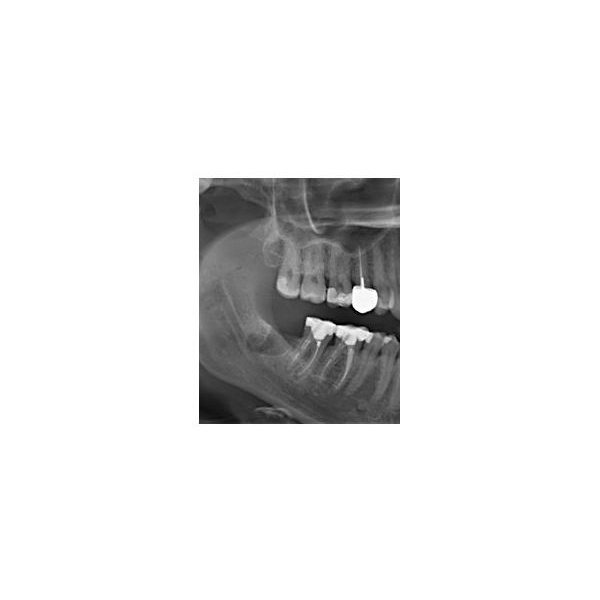

По результатам конусно-лучевой компьютерной томографии (КЛКТ) от 23.10.2022 года, в корневых каналах зуба 4.8 выявили следы пломбировочного материала, не доходящего до верхушки корня. В этой области отмечался овальный очаг разрежения кости с отчётливыми границами размером около 0,5 см в поперечнике.